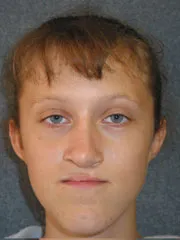

Cleft Lip and Palate

before |

after |